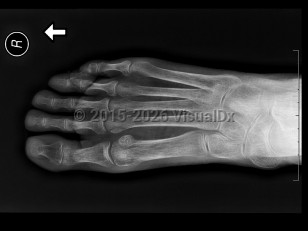

GoutGout